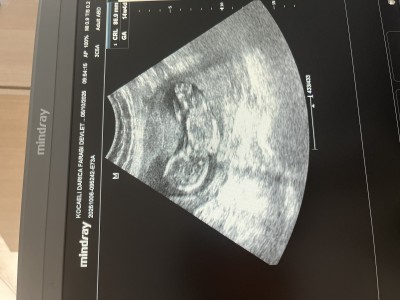

14+4 görüntüsü doktor önce baktı bacak kapalı göremedim dedi sonra kontrole devam etti tam biterken kıza benzettim dedi sizden tahmin alsam :)

Gebelik haftası 14+6